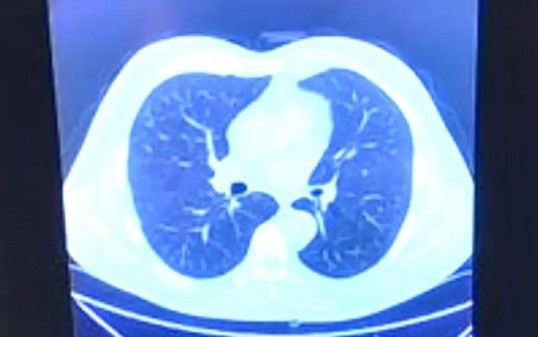

Tomografía del lunes 14 que muestra lesiones.

Se determina que presenta neumonía viral.